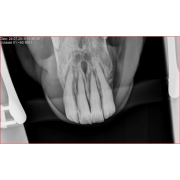

Bitplattorna är utvecklade speciellt för intraoral röntgen av framtänder utan att skymma något viktigt i exponeringen.

De radiolucenta bitplattorna har testats i enlighet med DAkkS-DKD-R 3-3 regelverket och kan stå emot ett tryck på 5,13 kN / 513 Kg.